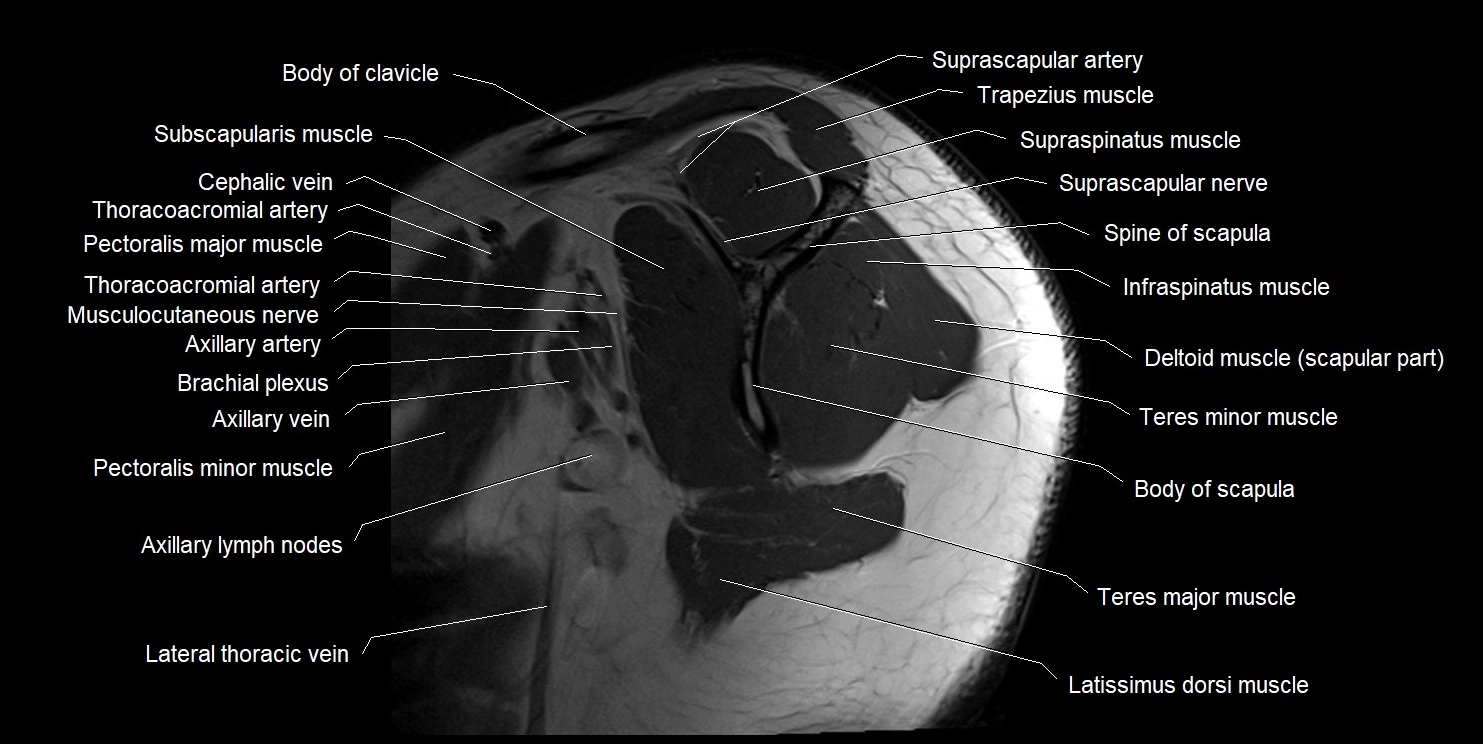

MRI images

image